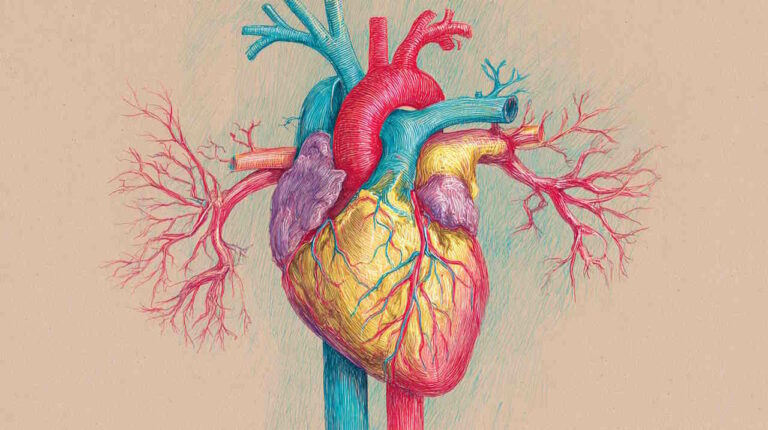

آناتومی ریه

ریهها اندامهایی با بافت اسفنجی و قابلیت اتساع بالا هستند که بهوسیله نایژههای اصلی به نای و بهوسیله رگهای خونی به قلب متصل میشوند. اطراف هر ریه غشایی از بافت سروزی به نام پرده جنب قرار دارد. این غشا از لایه احشایی و جداری تشکیل شده است. لایه احشایی به سلولهای خارجی ریه و لایه جداری به دیواره داخلی قفسه سینه، مهرههای پایینی گردن، مهرههای کمری دندهها انتهای قفسه سینه (Costovertebral Area)، مدیاستن و دیافراگم متصل میشود. بین این دولایه حفره جنب قرار دارد. این فضا از مایع سروزی پر شده و که با کاهش اصطکاک حرکت دو لایه پرده جنب در تنفس را تسهیل میکند. راس هر ریه بخشی گنبدیشکل است که بالاتر از اولین دنده قفسه سینه و قاعده آن نزدیک دیافراگم قرار دارد. دیافراگم ریه چپ را از معده و طحال و ریه راست را از کبد جدا میکند.

هر ریه از یک سطح دندهای، یک سطح میانی و یک سطح دیافراگمی تشکیل شده است که با سه لبه بالایی، پشتی و پایینی تقسیم میشوند. ریه راست بهوسیله دو شیار به سه لوب و ریه چپ بهوسیله یک شیار به دو لوب تقسیم میشود. هر لوب به بخشهای عملکردی (برونشیوپالمونری) تقسیم میشوند که بهوسیله بافت پیوندی از هم جدا شده و نایژهها و رگهای خونی مستقل دارند.

- ریه چپ: ریه چپ نزدیک قلب قرار دارد. به همین دلیل کمی از ریه راست کوچکتر است. اگر سطح جلویی ریه را یک ساعت در نظر بگیریم، شیار مورب از عدد ۱۰ شروع شده و به عدد ۵ وصل میشود. لوب بالایی ایجاد شده بهوسیله این شیار کوچکتر از لوب پایینی است و شامل بیشتر سطح دندهای و میانی و نوک ریه میشود. فرورفتگی قلب در لوب بالایی قرار دارد.

- ریه راست: عرض ریه راست از ریه چپ بیشتر و طول آن کوتاهتر است. این اندام بهوسیله دو شیار مورب و افقی به لوبهای بالایی، میانی و پایینی تقسیم میشود. شیار افقی هیلوم (همسطح غضروف دندهای چهارم) را به سطح جلویی و میانی وصل میکند. لوب میانی کوچکترین بخش ریه راست است.